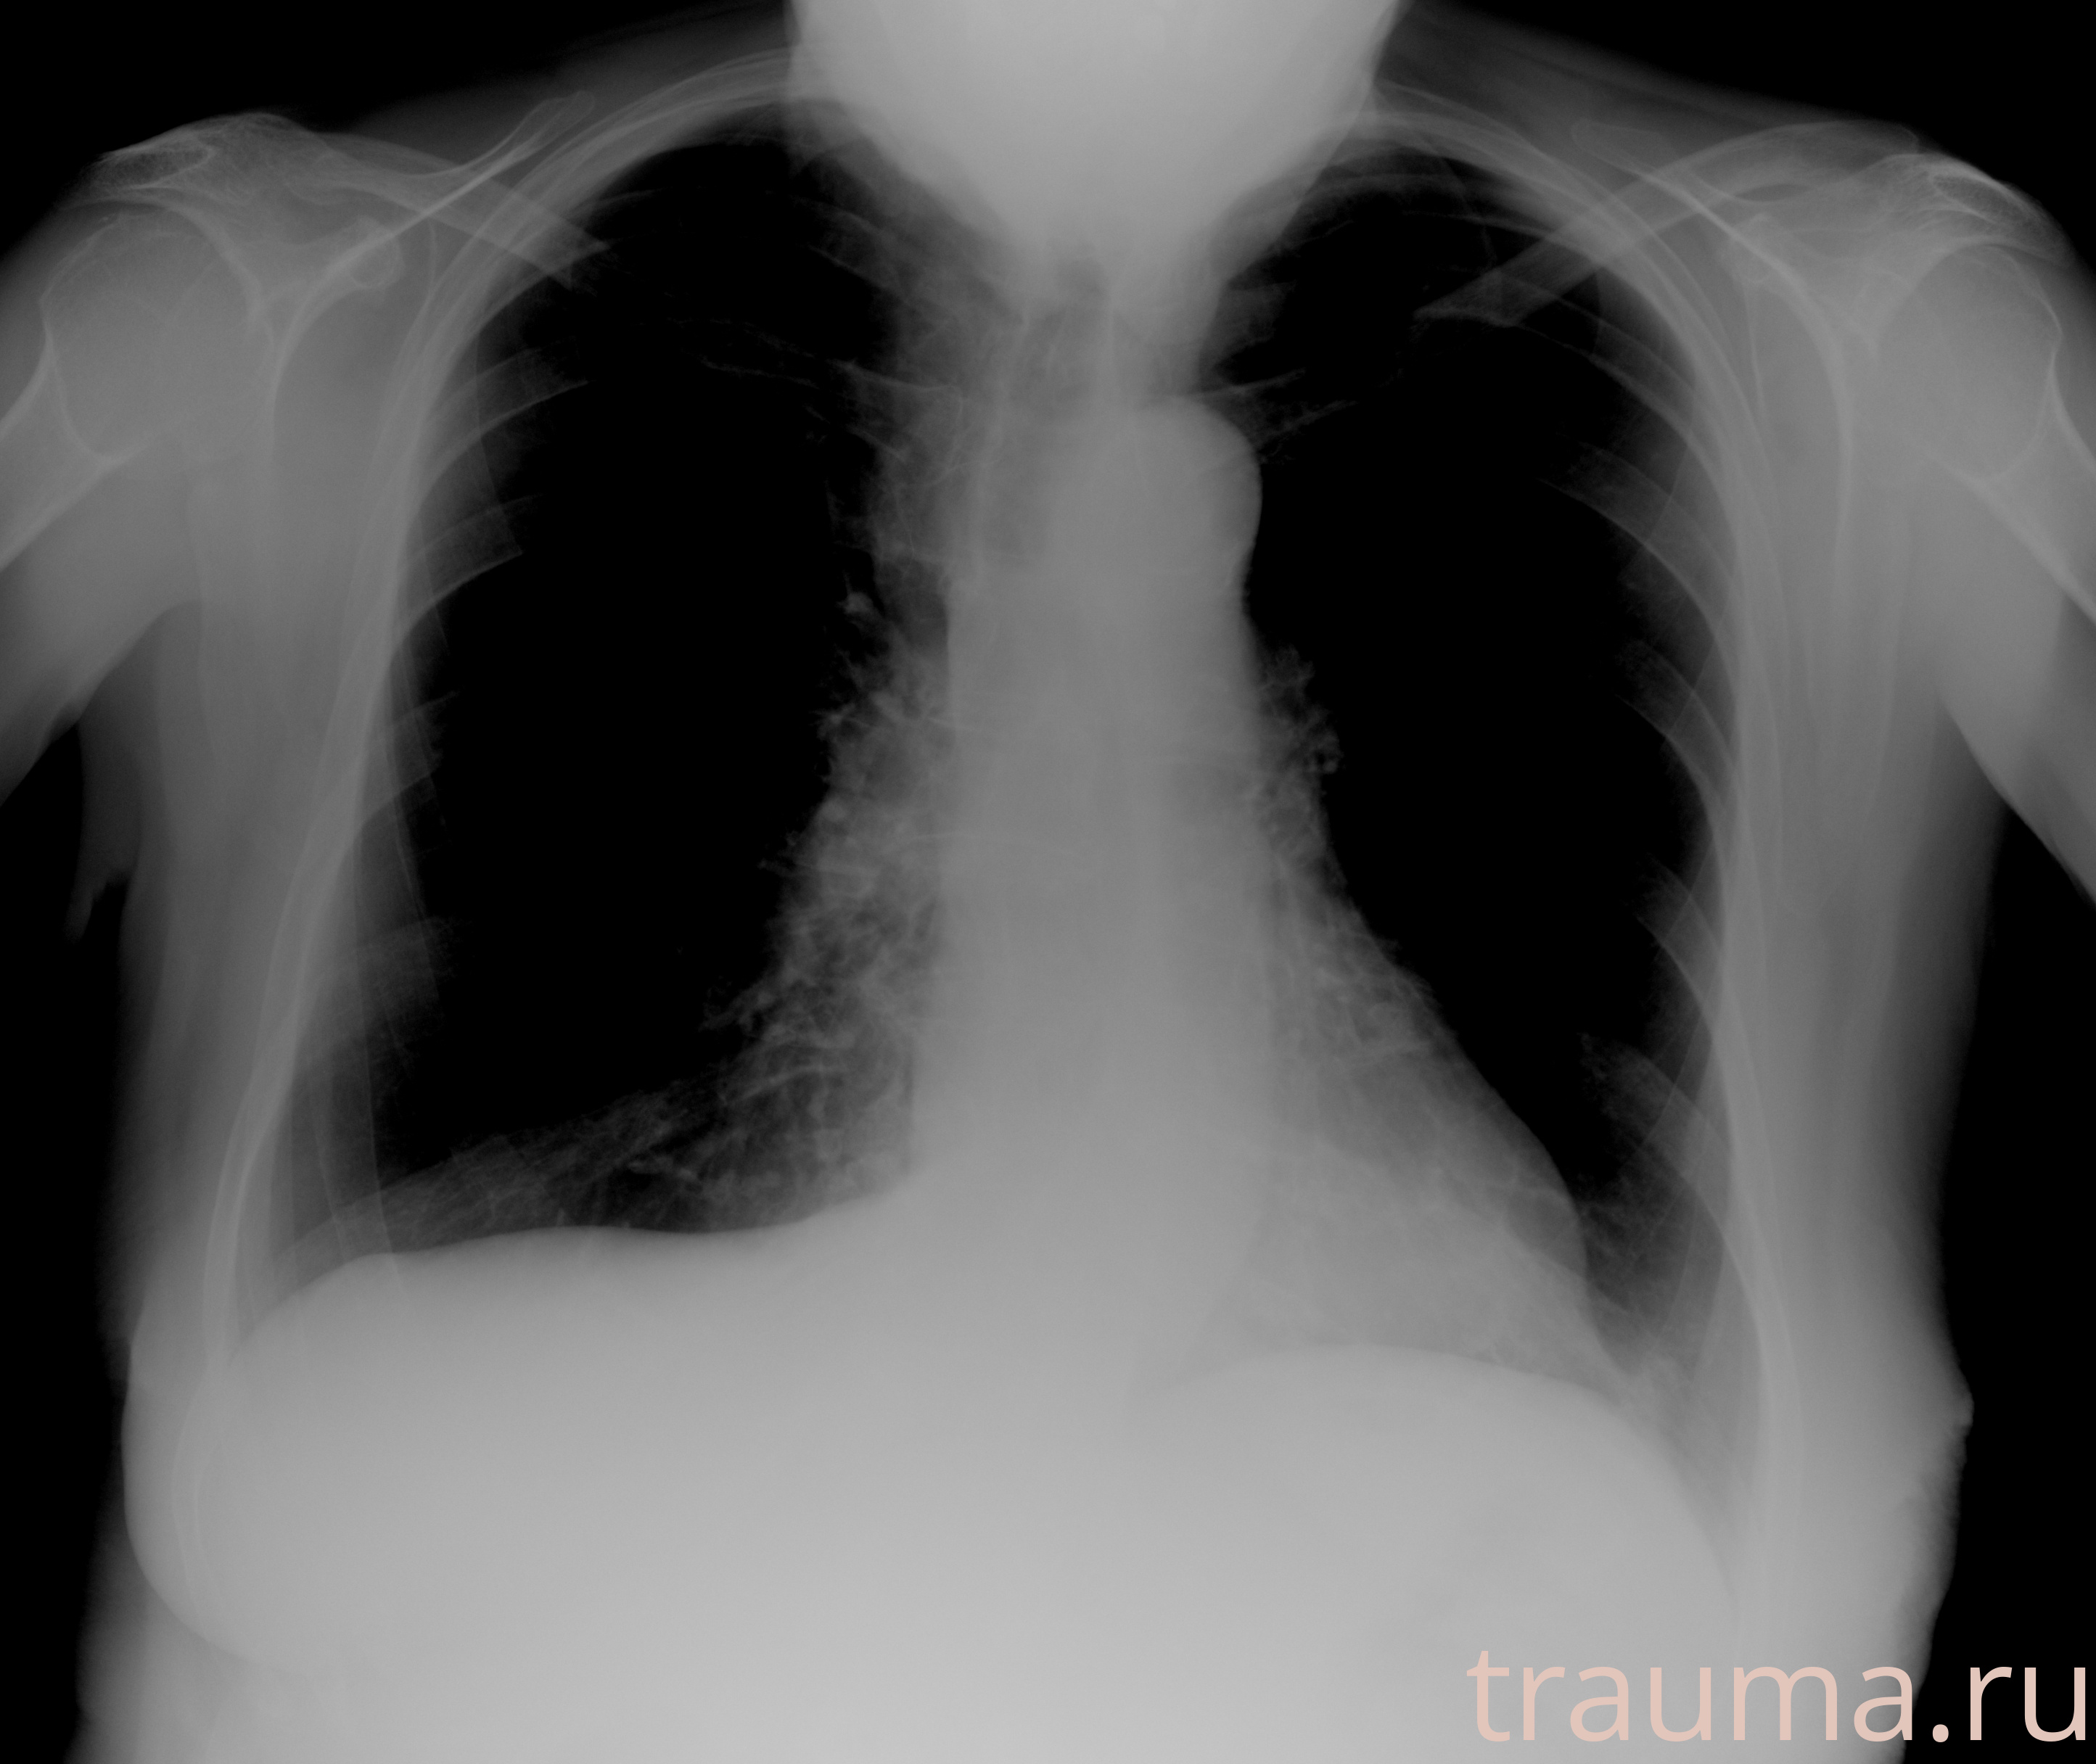

Рентгенограммы

Рентген на дому: по вашему адресу приезжает врач-рентгенолог, травматолог-ортопед с мобильным рентгеновским аппаратом, проводит диагностику травмы или заболевания, делает необходимые рентгенограммы, дает рекомендации по дальнейшему лечению. Получить качественные снимки в домашних условиях возможно благодаря уникальной методике, разработанной МосРентген Центром для института  Склифосовского